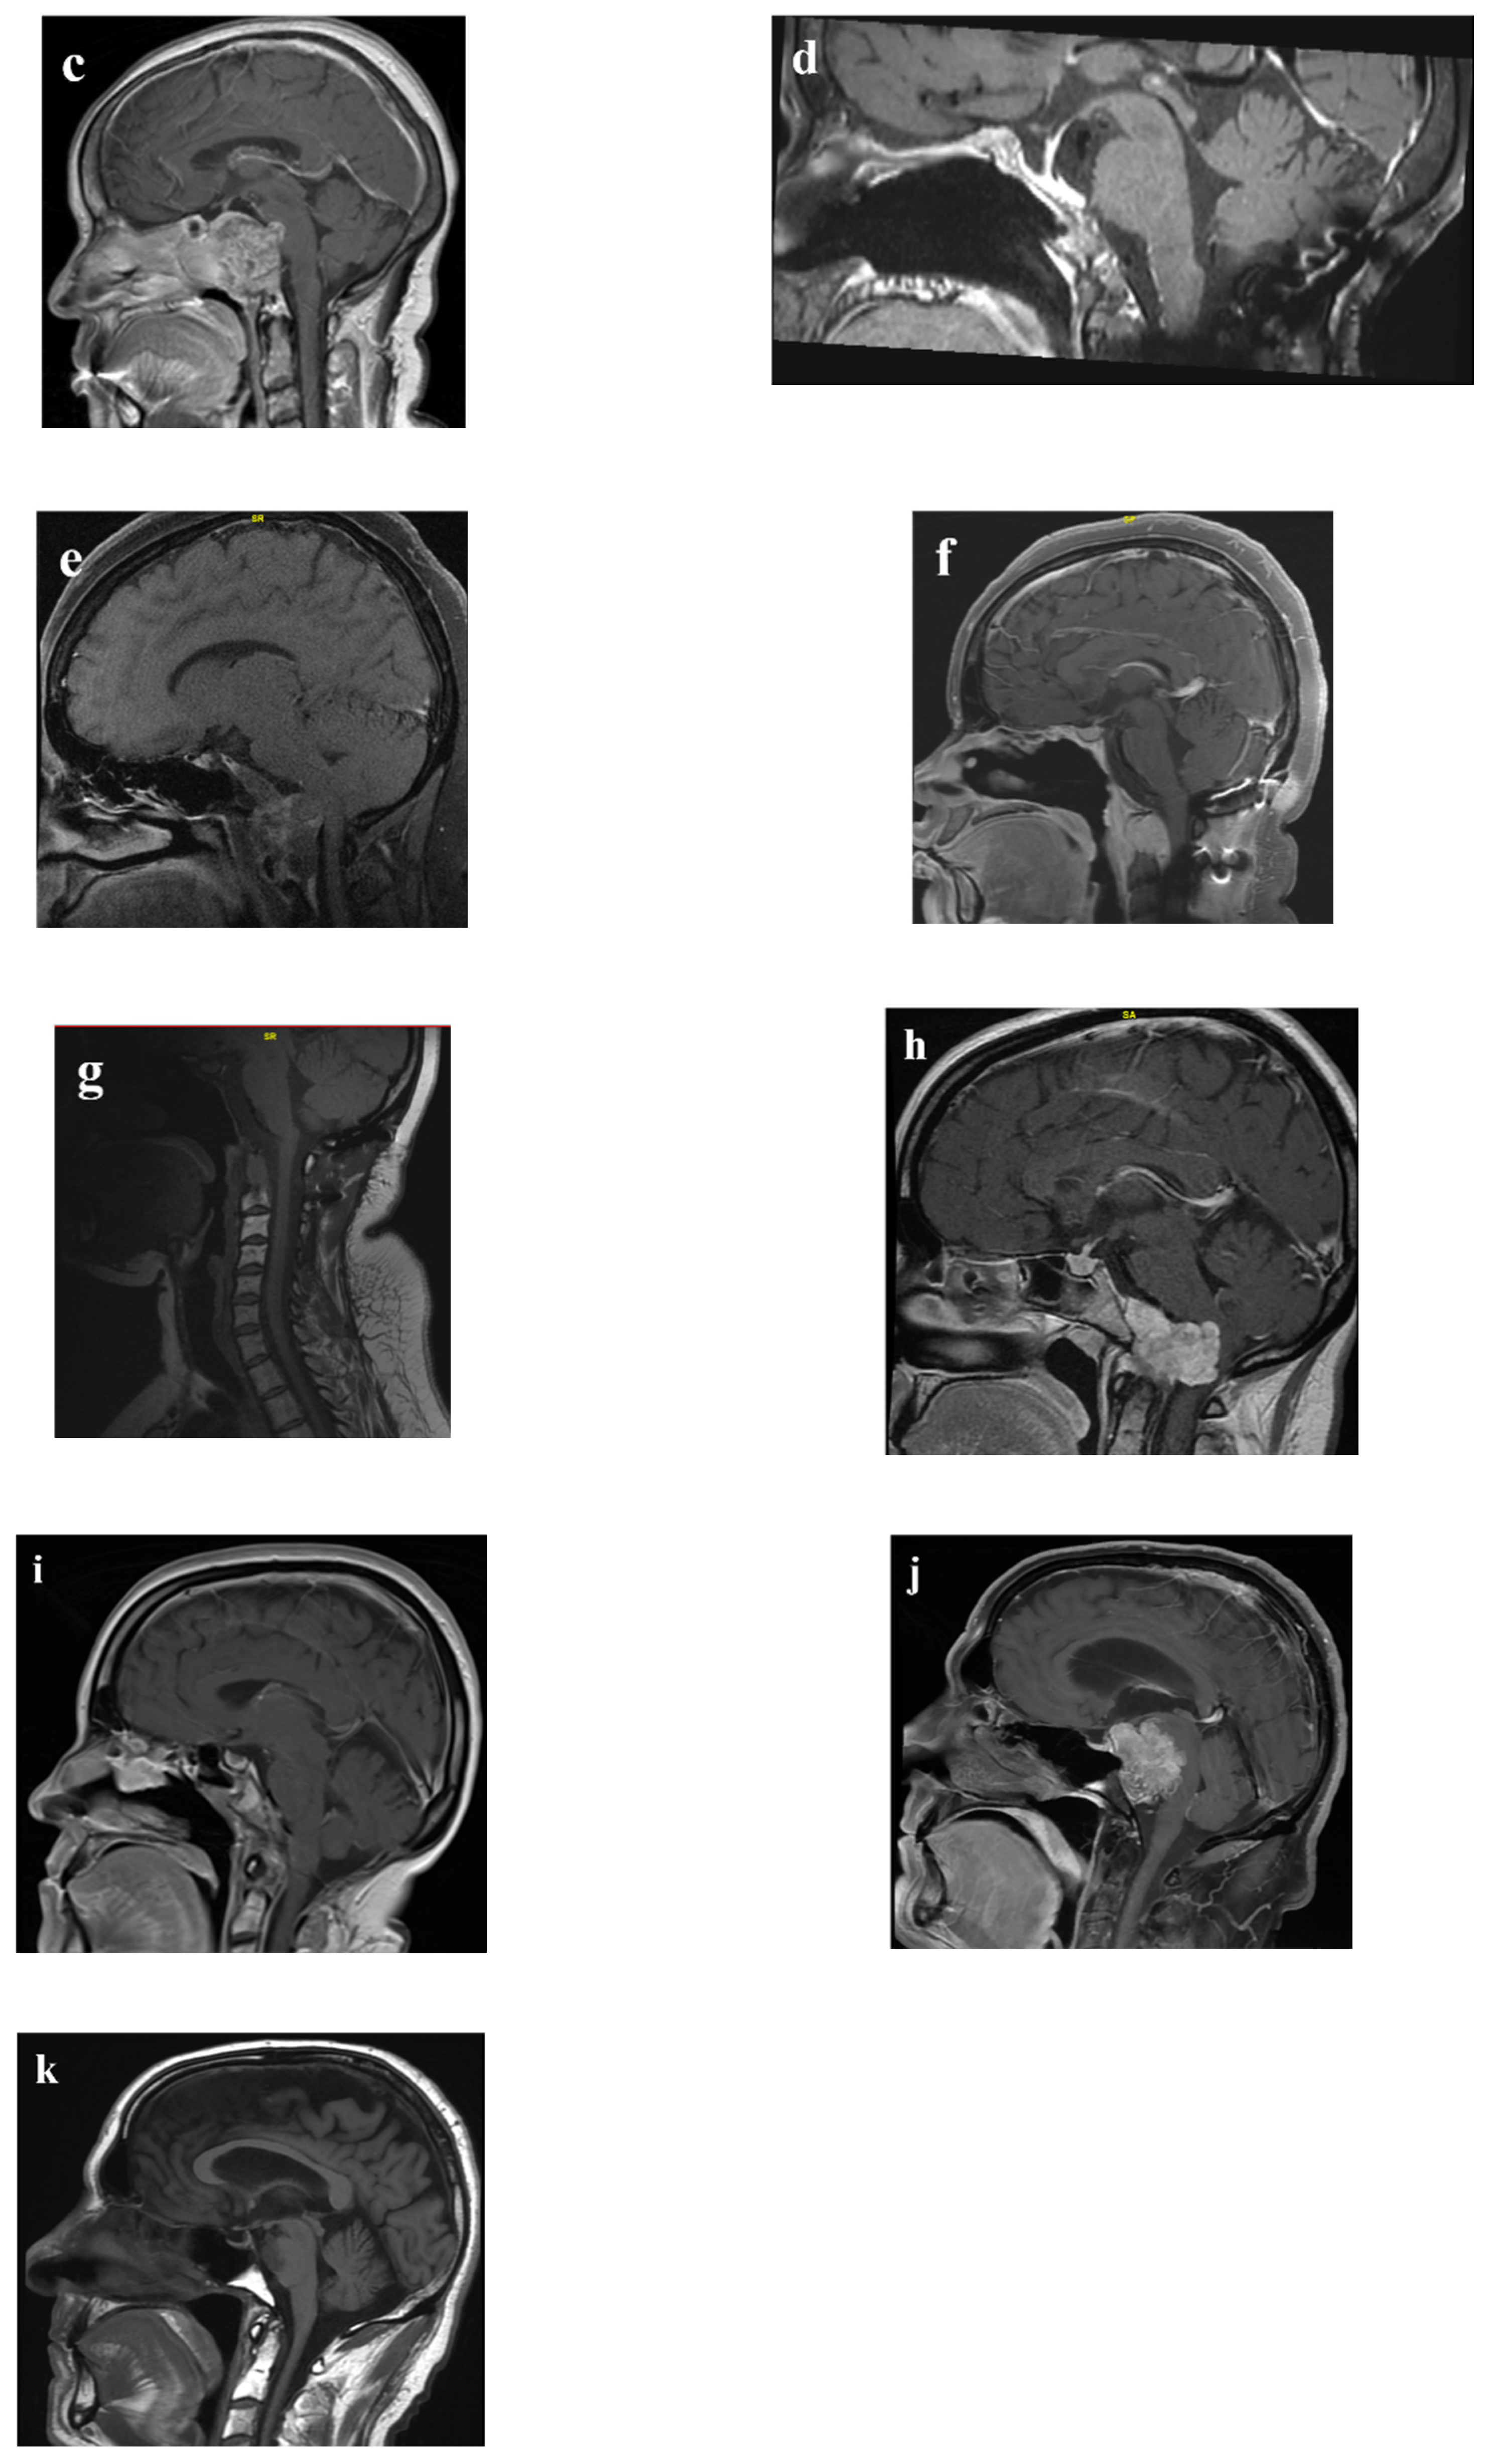

| Operative approach | 36 | - | ||

| EEA | 1 | 6 (32%) | 30 (77%) | |

| Endoscopic transcervical | 4 | 0 | 1 | |

| MicroEA | 10 | 4 | 0 | |

| Open craniotomy | 2 | 7 | 3 | |

| EEA, open craniotomy | 2 | 0 | 2 | |

| EEA, OC fusion | 12 | 0 | 2 | |

| EEA, OC fusion, endoscopic transcervical | 0 | 1 | ||

| Midline mandibular osteotomy | 2 | 0 | ||

| Degree of resection | 0.002 | |||

| GTR or NTR | 28 | 3 (16%) | 25 (64%) | |

| STR | 30 | 16 | 14 | |

| The location of residual tumor after STR | - | |||

| EEA | ||||

| Posterior to paraclival ICA, petrous apex, cavernous sinus | 8 | 3 | 5 | |

| Dorsum sella, cavernous sinus | 2 | 1 | 1 | |

| Prepontine cistern (attached to the pons) | 1 | - | 1 | |

| Sella, sphenoid sinus, clivus | 2 | 1 | 1 | |

| Endoscopic transcervical | ||||

| Peri-odontoid space | 1 | - | 1 | |

| MicroEA | ||||

| Posterior to paraclival ICA | 1 | 1 | - | |

| Image unavailable | 3 | 3 | - | |

| Open craniotomy | ||||

| Various sites (refer to the manuscript) | 6 | 3 | 3 | |

| EEA, open craniotomy | ||||

| Posterior suprasellar region | 1 | - | 1 | |

| EEA, OC fusion, endoscopic transcervical | ||||

| Prevertebral space of the craniovertebral junction | 1 | - | 1 | |

| Midline mandibular osteotomy | ||||

| Image unavailable | 1 | 1 | - | |

| New cranial nerve deficits | 7 | 6 (32%) | 1 (2.6%) | 0.004 |